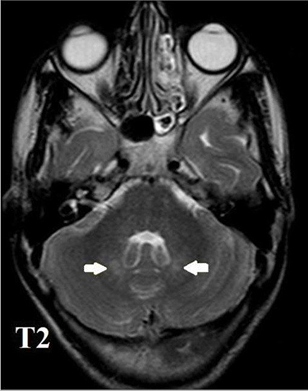

МРТ головного мозга: симметричный Т2-/FLAIR- гиперинтенсивный сигнал от зубчатых ядер мозжечка, задних ножек внутренней капсулы См РИС

🧠 Нейровизуализация:

• двустороннее поражение зубчатых ядер мозжечка (симметричная гиперинтенсивность в режимах Т2 и FLAIR);

МРТ головного мозга